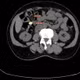

Qua thăm khám và chẩn đoán hình ảnh, các bác sĩ xác định dị vật là một đồng xu thép có đường kính khoảng 3 cm, nằm ở 1/3 dưới thực quản – vị trí tiềm ẩn nhiều nguy cơ nếu không được xử trí kịp thời.

22-gio-dem.jpg

Đồng xu được lấy ra an toàn - Ảnh BVCC